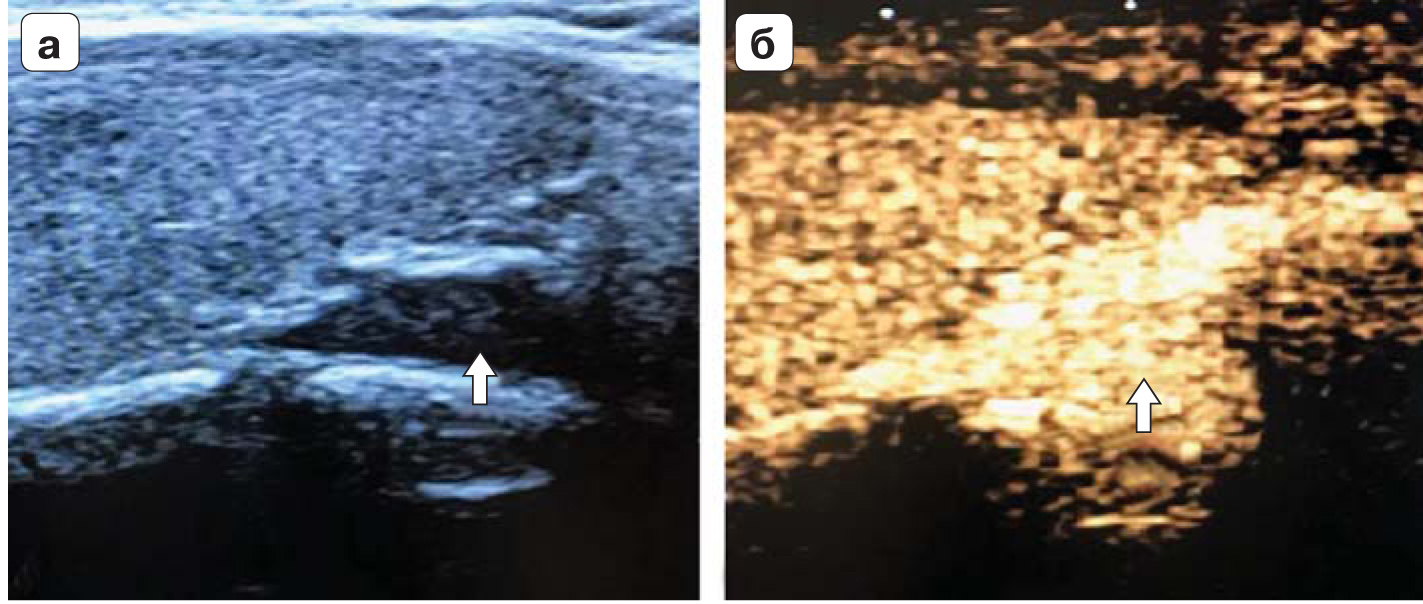

3. Fig. 2. a - ultrasound, with a longitudinally located sensor hypoechoic formation (thin arrow) behind the left lobe of the thyroid gland (thick arrow); b - in the color Doppler mode, hypoechoic formation of the thyroid gland (thin arrow) with typically enhanced vascularization at one of the poles (thick arrow) (images from Diagnostic Imaging: head and neck, 3rd edition, Elsevier 2017). | |